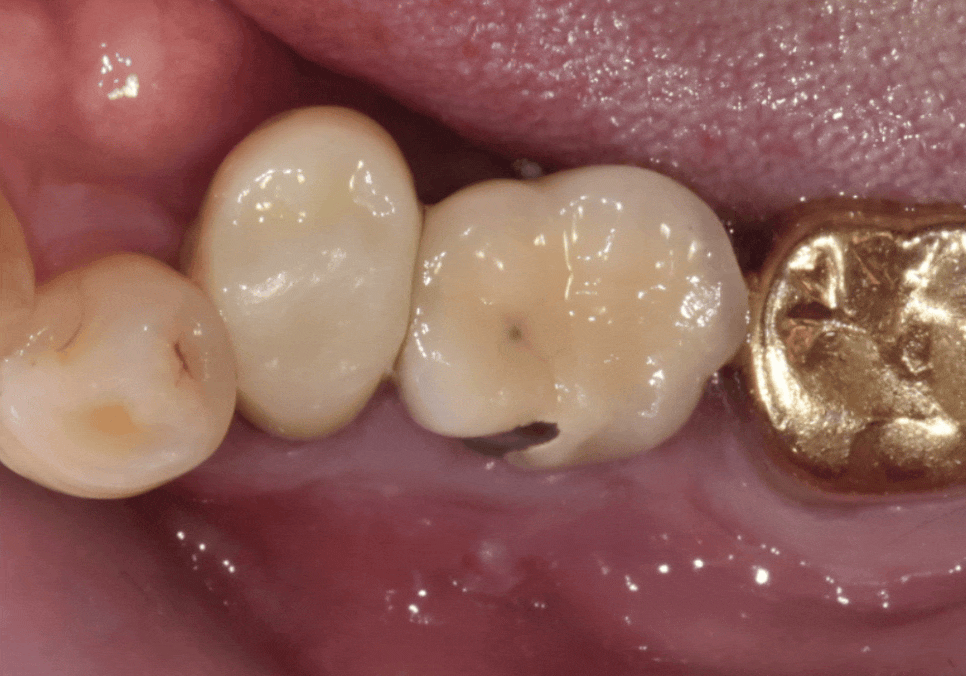

3개월 뒤,잇몸뼈가 단단하게

잘 아문 것을 확인하고

보철물 제작 단계로 들어갔어요.

환자분께서 가장 힘들어하셨던

음식물 끼임 문제를 해결하기 위해,

이번에는 새로 심은 임플란트(#35)와

기존 임플란트(#36)를

하나로 튼튼하게 연결하는

스플린트(Splint) 방식을 선택했습니다.

두 개의 보철물을 각각 따로 만들지 않고

하나로 묶어주면,

치아 사이에 틈이 생기지 않아

음식물이 들어갈 자리를

원천적으로 차단할 수 있거든요.

240106 (전) 240706 (후)